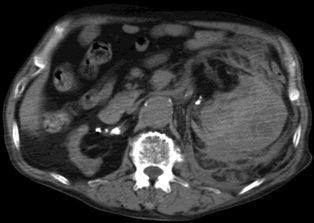

腹腔 动脉造影发现造影剂外溢,但供血动脉似乎来自于胃十二指肠动脉,但不确定 |